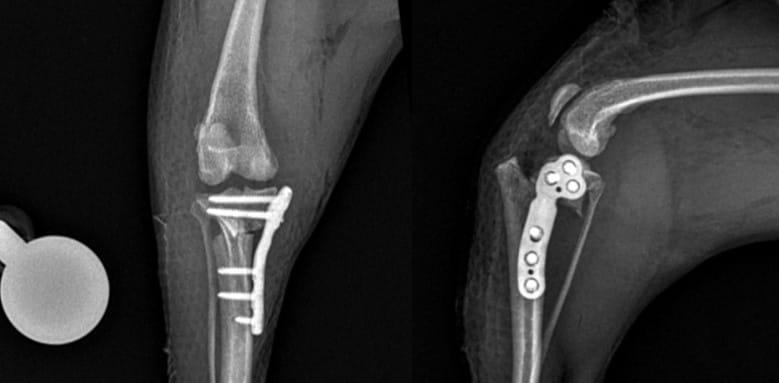

노령견 십자인대파열 수술 특화 시스템 구축TPLO 수술을 받은 반려견 영상 사진(예은동물의료센터 제공) ⓒ 뉴스1권기범 황은혜 남태훈 수의사(예은동물의료센터 제공) ⓒ 뉴스1관련 키워드펫헬스케어동물반려동물최서윤 동물문화전문기자 "반려동물 보호자에 진짜 정보 주고파…강력한 처방전은 공감"가축방역 하느라 집에도 못 간다…"수의사, 빛과 소금 같은 존재"관련 기사"간식 양보해 줄 남친 구함"…15살 노견 공개 구혼에 댓글 폭주"댕댕이 여름 산책룩 준비"…BYC, 부산서 신상 '개리야스' 공개체험형 '펫푸드 키친' 공개…우리와, 케이펫페어 부산 출격법정전염병이라면서…"광견병 의무접종, 시술비도 지원 필요""대국민 소통 확대"…대한수의사회, 임원 워크숍서 위상 강화 계획